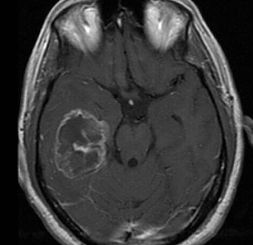

The following morning after running more tests, it was confirmed that he had brain cancer. Glioblastoma Multiforme Grade 4 to be exact. The circle to the left is the tumor.